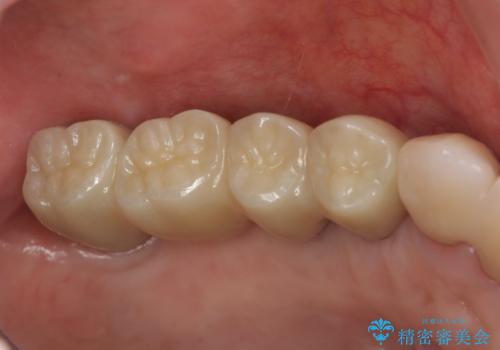

奥歯を多数失い全く噛めない期間があり、困り果てて来院されましたが、インプラント治療をおこなったことでしっかりと噛めることができるようになりまた食事を楽しめるようになったと大変喜んでいただくことができました。

- 275万円(インプラント×5・チタンカスタムアバットメント×5・ジルコニアクラウン×7・仮歯×7)費用は治療当時の料金となります